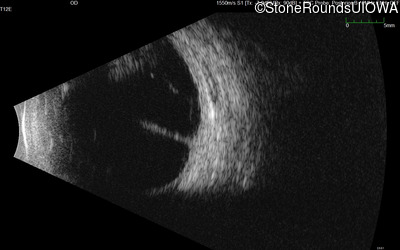

B-Scan Ultrasonography - Right - 20/600

Exemplar